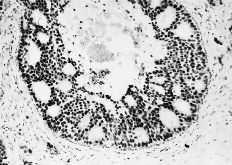

Las cuatro observaciones mostraron positividad a los RE con histocores superiores a 100. La evaluacion inmunomorfológica de los RE arrojó cifras de histocore hormonal (HH) comprendidas entre 108 y 300, con intensidades de ++/+++, en un porcentaje celular comprendido entre el 36 y el 75% (Figs. 1 y 2). La positividad a los RE se manifestaba por la presencia de inmunotinción especifica nuclear. En general, la positividad a los RE mostró un carácter de heterogeneidad de forma que no todas las áreas tumorales presentaban el mismo nivel de positividad o bien existían diferentes porcentajes en el número de núcleos marcados. En dos casos existían en periferia a las áreas tumorales imágenes de ginecomastia proliferativa, que asimismo mostraba positividad al receptor estrogénico (Fig. 3). En un caso (HH de 108) asimismo se cuantificaron en 230 fmol/mg ADN los REn mediante el método bioquímico DCC.

Fig. 3. Área de ginecomastia en el tejido mamario peritumoral con positividad asimismo para el REn. (ERICA, 200*.)

El estudio inmunohistoquímico practicado en las muestras tisulares de nuestros pacientes demostró en todos ellos la presencia de receptores hormonales estrogénicos, observándose asimismo en dos de ellos en las áreas de ginecomastia la presencia de RE+. Así, los cuatro casos estudiados de carcinoma ductal infiltrante afectando a varones pueden ser considerados desde esta perspectiva como cánceres mamarios hormonodependientes. Nuestra determinación inmunohistoquímica mediante el método ERICA se vio refrendada en un caso por un cuantificación de los REn mediante el método bioquímico DCC. Nuestros datos, a pesar del muy limitado número de observaciones, apoyan la hipótesis del frecuente carácter de hormonodependencia del cáncer de mama en el varón.